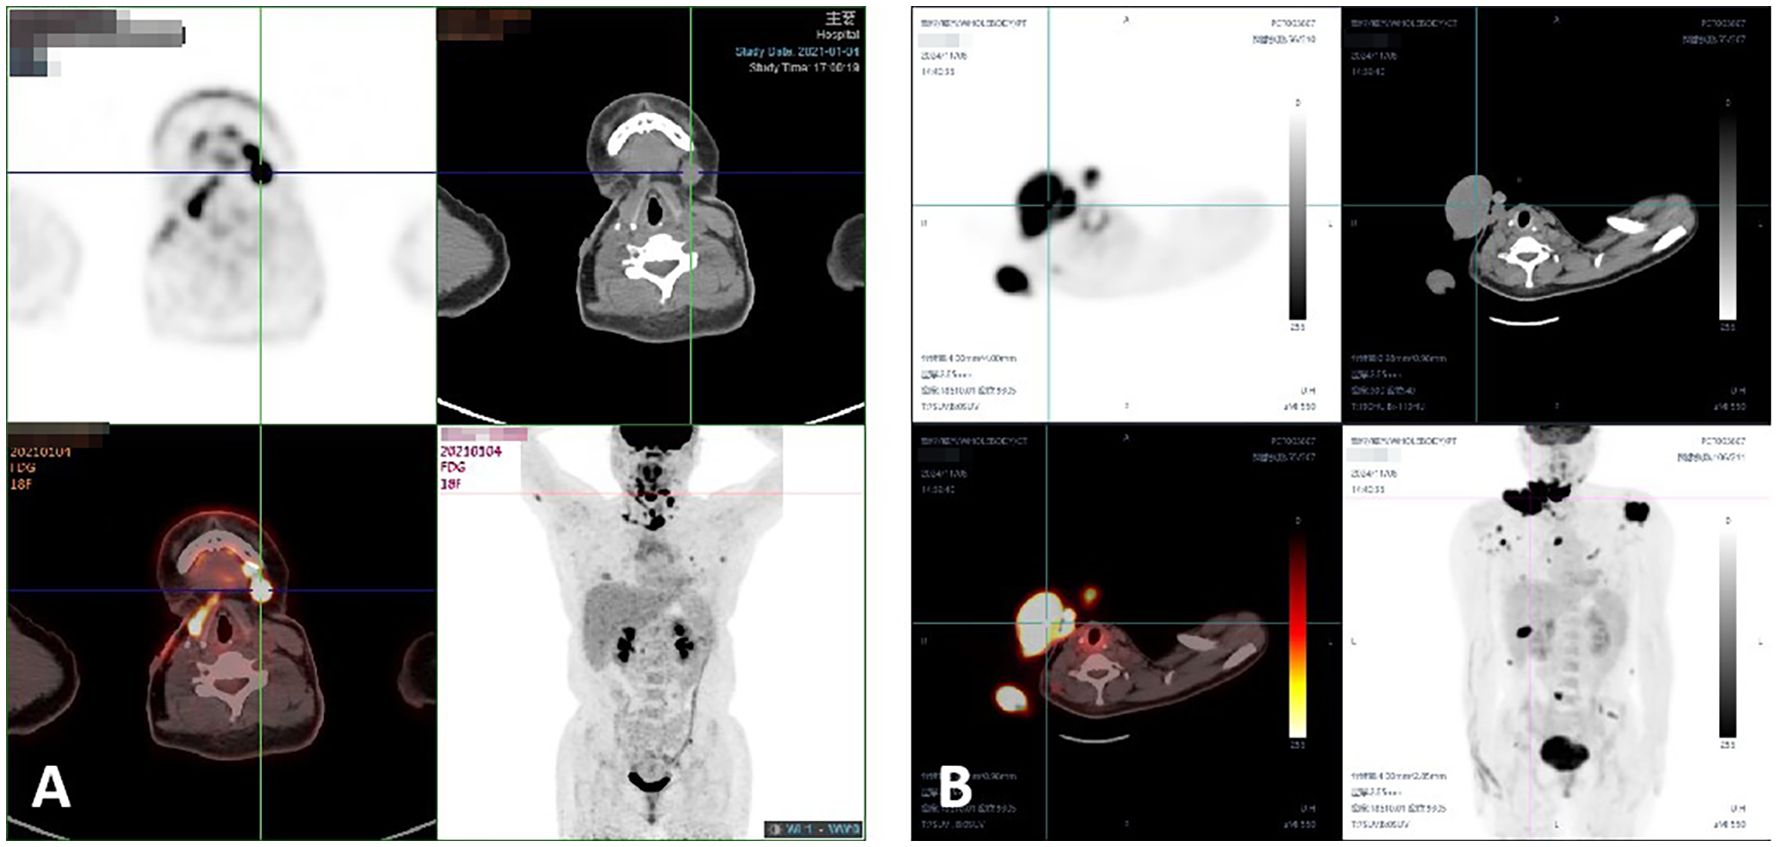

Background: Benign Fibrous Histiocytoma (BFH), also known as dermatofibroma, is a common benign mesenchymal tumor of the skin. Although typically non-aggressive, rare cases of metastatic BFH pose diagnostic and therapeutic challenges. Methods: This study reviews 10 cases of metastatic BFH diagnosed at Fudan University Shanghai Cancer Center between 2009 and 2024, with a detailed examination of three cases involving recurrent and metastatic behavior. Immunohistochemical markers and radiological imaging findings were analyzed to characterize tumor progression and treatment responses. Results: The cases highlighted distinct patterns of recurrence and metastasis, including lymphatic and distant organ involvement. Immunohistochemical analysis demonstrated variable expression of markers such as Vimentin, CD68, CD163, Ki67, and SMA. Conclusions: Metastatic BFH remains a rare but clinically significant condition. Early recognition, accurate histopathological diagnosis, and multimodal therapies are crucial for effective management.